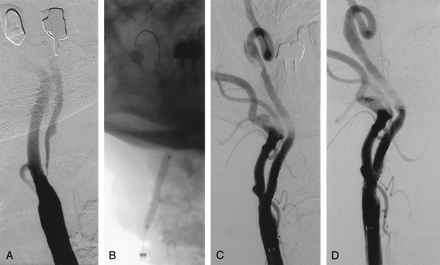

Between February 2000 and September 2002, 303 patients (325 carotid arteries) underwent carotid artery stent placement with a distal balloon antiembolization system (GuardWire Temporary Occlusion and Aspiration System; Medtronic AVA, Danvers, MA) (Fig 1). All patients were treated under a prospectively defined protocol that was approved by the institutional review board, and all gave written informed consent for the procedure. Patients were referred based on duplex ultrasonographic or MR angiographic findings. All patients underwent cervicocerebral angiography in our laboratory and were enrolled in this protocol if they were symptomatic (38%) or asymptomatic (62%) with extracranial internal carotid artery (ICA) stenosis of 50% or greater, or 70% or greater, respectively, based on North American Symptomatic Carotid Endarterectomy Trial criteria. Quantitative carotid angiography was performed before and after the procedure. Included in the protocol was a neurologic examination performed by an independent board-certified neurologist before and immediately after completion of the stent placement procedure, and at 30 days and 6 and 12 months after the procedure. Patients were excluded from the study for the following reasons: stroke within 7 days before the procedure; baseline neurologic deficit that was likely to confound determination of the study clinical end points (National Institutes of Health Stroke Scale [NIHSS] score ≥ 15); more than one ipsilateral carotid stenosis requiring treatment; a cardiac source of emboli such as atrial fibrillation; the presence of known intracranial tumor or vascular malformation; contralateral carotid artery occlusion, severe ipsilateral intracranial carotid stenosis, and insufficient or nonexistent collateral blood supply to the ipsilateral hemisphere; and renal insufficiency (serum creatinine level ≥ 2.5 mg/dL).

The GuardWire protection system.

Optimal utilization of the occlusion balloon antiembolization strategy is dependent on patient and lesion selection and appropriate application of the system by using various technical maneuvers to overcome anatomic challenges. Advancing the GuardWire temporary occlusion catheter into a moderate stenosis with a nonangulated bifurcation or with only a moderately angulated takeoff of the ICA poses no technical challenge (Fig 2). In both instances, the extended tip of the temporary occlusion catheter can be shaped and the system can be easily negotiated through the stenotic lesion. However, in cases of preocclusive stenoses, heavily calcified or eccentric lesions, severe distal kinks or tortuosity of the ICA, especially when the ICA takeoff is considerably angulated, it can be difficult and sometimes impossible to advance the temporary occlusion catheter into the distal ICA (Figs 3 and 4). In these situations, placement of a side wire or “buddy wire,” eventual gentle predilation, or a combination of both (Fig 3) may facilitate advancement of the temporary occlusion catheter.

Application of the GuardWire protection system in a 62-year-old man with recent multiple transient ischemic attacks.

A, Right carotid angiogram shows significant stenosis in the ICA.

B, Angiogram shows that the balloon on the temporary occlusion catheter is inflated in the distal cervical segment of the ICA (stent is deployed and postdilated).

C, Carotid angiogram obtained after stent placement.

Device Description

The GuardWire system is designed to contain embolic material released during stent placement, preventing the material from reaching the cerebral circulation. The GuardWire is a temporary occlusion and aspiration system that has three components: the temporary occlusion catheter, the MicroSeal adapter, and the Export aspiration catheter. The temporary occlusion catheter is a “balloon-on-a-wire” catheter with a distal elastomeric occlusion balloon (Fig 1). It has a lubricating coating and a flexible radiopaque tip. Crossing profile is 0.036-inch (1 mm, 2.9F). The MicroSeal adapter is used with the temporary occlusion catheter (Fig 1) for the purpose of controlled volumetric inflation and deflation of the occlusion balloon. The first generation of the GuardWire, used earlier in this study, allowed the occlusion balloon to be inflated to two sizes: 5.5 and 6 mm. The second and present generation version has an inflation device that can be set to inflate the occlusion balloon to between 3 and 6 mm in 0.5-mm increments. The Export aspiration catheter is a monorail design that has a distal radiopaque tip marker and a proximal Luer-Lock port. The older GuardWire system had a 300-cm-long 0.018-inch temporary occlusion catheter; the present system is a 0.014 inch and 190 cm temporary occlusion catheter. Because of the shorter length of the current generation GuardWire catheter, only monorail balloons and stents can be used.